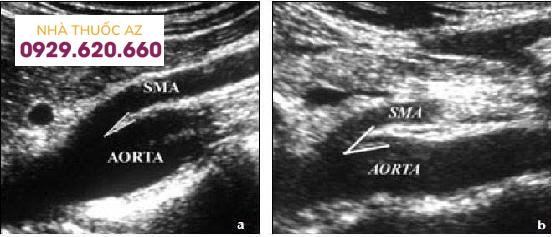

Bệnh nhân nữ 7 tuổi, đau bụng trên, nôn dịch mật, ăn không ngon và sụt cân. Cân nặng 21kg, cao 1.23 m (cân nặng nhỏ hơn chiều cao). Không khai thác được bất cứ tiền căn về rối loạn tâm lý và quá trình tăng trưởng và phát triển. Nhập viện trong tình trạng lờ đờ, mất nước vừa, tim 100l/p, HA 116/63 mmHg, nhiệt độ 370. Khám lâm sàng bình thường. Hình A, tái tạo Sagittal đo góc hẹp 14 độ. Hình B, đo khoảng cách hẹp 11 mm. Siêu âm: góc ĐMTTT và ĐM chủ bụng = 10 độ

Mặt cắt dọc và ngang trên siêu âm của bệnh nhân này cho thấy hẹp góc và khoảng cách ĐMTTT và ĐM chủ bụng. Nguồn: Usman Javaid, A.R. Mustafawi, Munir ahmad. The Superior Mesenteric Artery Syndrome (SMAS): Is it really a diagnostic dilemma? Annals of Pediatric Surgery Vol 5, No 3, July 2009, PP 206